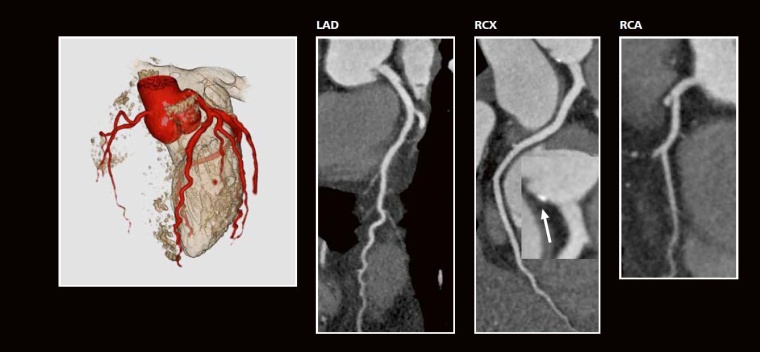

CT -Angiographie:

Linksversorgungstyp mit sehr klein angelegter RCA (3D-Bild). In der multiplanaren Rekonstruktion (Curved MPR) Ausschluss von kalzifizierten und nicht-kalzifizierten arteriosklerotischen Plaques. Aber diskrete Kalzifikation in der Aortenwurzel (Vergrößerung Mitte, Pfeil) als Beweis einer beginnenden Arteriosklerose in sehr jungem Alter. Strahlendosis CTA = 1,8 mSv.